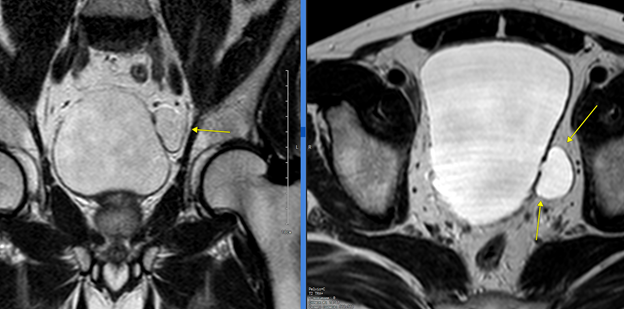

Рис. 2. Псевдодивертикулы задней и передней стенок мочевого пузыря. [3]

Псевдодивертикулы (приобретенные) возникают как следствие обструкции выходного отверстия мочевого пузыря. Наиболее частыми причинами возникновения псевдодивертикулов у взрослых являются гипертрофия предстательной железы, нейрогенный мочевой пузырь, стриктура уретры [3].